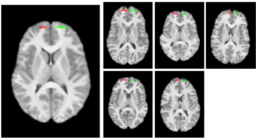

The structural atlas built from the five T1 images with manually outlined frontal forceps seeds (left). The seeds mapped to each of the individual cases (right).